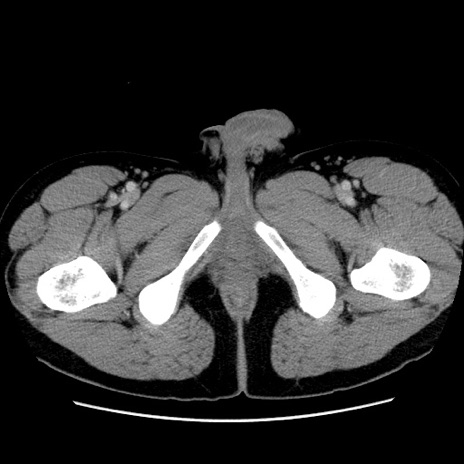

症例4(横断像)

【症例】30歳代男性

【主訴】腹痛、嘔吐

【現病歴】昨晩から突然の腹痛あり、その後嘔吐、軟便も出現。腹痛が改善しないため救急搬送となる。2日前にしめ鯖の食事歴あり。

【身体所見】意識清明、苦悶様、BP 135/90mmHg、BT 35.7℃、腹部:平坦、やや硬、心窩部〜臍部に自発痛、圧痛あり、筋性防御+、反跳痛-

【データ】WBC 8100、CRP 0.57